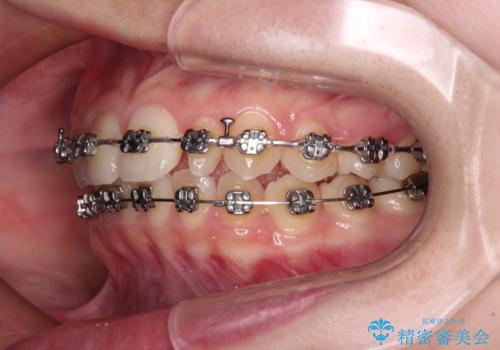

- 矯正装置

- メタルブラケット

- 1年1ヶ月

- 10-30回